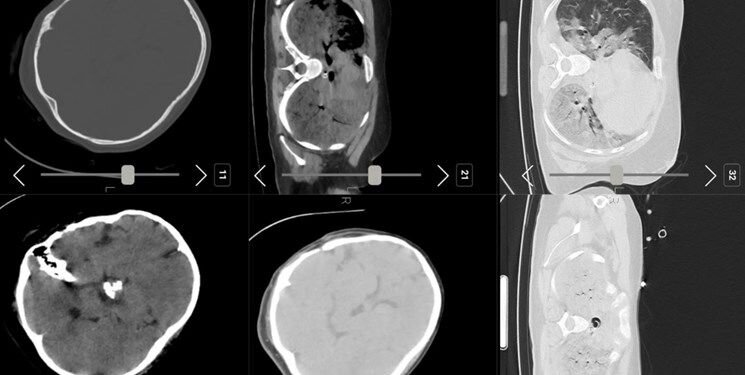

فارس: تصاویر سیتی اسکن مهسا امینی نشان می دهد او در سال های قبل جراحی سر داشته است

فارس نوشت: صبح امروز شبکه اینترنشنال عکسی از سی‌تی اسکن مرحوم مهسا امینی منتشر کرد و مدعی شد که «سی‌تی اسکن مهسا نشانگر شکستگی جمجمه، خون‌ریزی و ادم مغزی است»...متخصصان معتقدند بررسی‌های سی تی اسکن بیمارستان نشان می‌دهد هیچ شواهدی از ضربه به سر و خونریزی در این تصاویر به چشم نمی‌خورد.

با اینکه در ابتدا تصور می شد این تصاویر به مانند بسیاری از اخبار این رسانه جعلی باشد اما پیگیری های خبرنگار فارس از مراجع ذیربط نشان داد تصاویر سیتی اسکن منتشر شده مربوط به مرحوم #مهسا_امینی است.

فارس: تصاویر سیتی اسکن منتشر شده مربوط به مرحوم مهسا امینی  است

برای بررسی علمی این موضوع با تعدادی از پزشکان مغز و اعصاب و رادیولوژیست گفت‌وگو کردیم تا به صورت علمی این موضوع را بررسی کنیم. این متخصصان معتقدند بررسی‌های سی تی اسکن بیمارستان نشان می‌دهد هیچ شواهدی از ضربه به سر و خونریزی در این تصاویر به چشم نمی‌خورد.

یک متخصص جراحی مغز و اعصاب به خبرنگار ما گفت: بررسی‌ها نشان می‌دهد که بیمار در گذشته جراحی در ناحیه سر انجام داده است اما براساس شواهد موجود از روی سی‌تی‌اسکن نمی‌توان فهمید که جراحی دقیقاً مربوط به چند سال قبل است. همچنین شواهد کرانیتومی فرونتوتمپورال قبلی همراه با آتروفی مختصر عضلانی و تغییرات بافت نرم در محل جراحی بیمار مشهود است.

یکی دیگر از پزشکان مغز و اعصاب نیز جراحی تومور بیمار را تایید می‌کند. به گفته این متخصص مغز و اعصاب متاسفانه برخی از افراد با دیدن تصاویر ناقص سی تی اسکن درفضای مجازی اقدام به اعلام نظر کرده‌اند اما واقعیت این است که در تصاویر کامل اثری از شکستگی نیست و این رسانه سعودی تصاویر را از زاویه‌ای منتشر کرده است که شکستگی به نظر برسد.